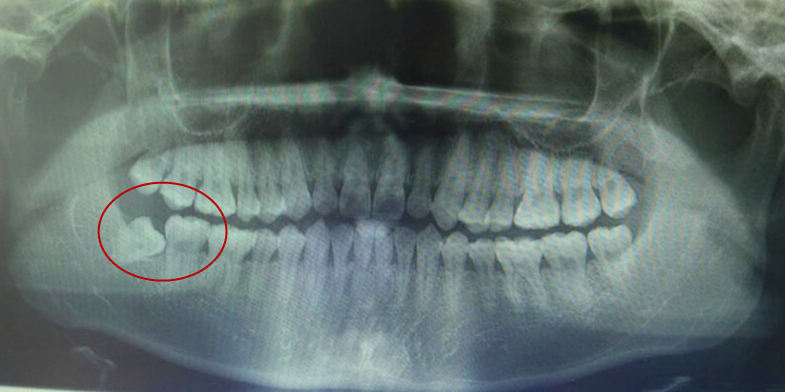

▽阻生牙会伤害邻牙

智齿长在肉里要拔掉吗?首先要拍片检查,确定牙齿的生长情况:

2、如何拍片后牙齿位置不正,无法长出还对旁边邻牙造成威胁的,应当尽早拔除。若智齿没有及时拔除导致邻牙蛀牙的例子很多。(80%的人的智齿位置长的都不正~)

三、长歪的智齿,也就是阻生智齿,也有可能因为位置不正,长不出来,埋伏在牙床里。